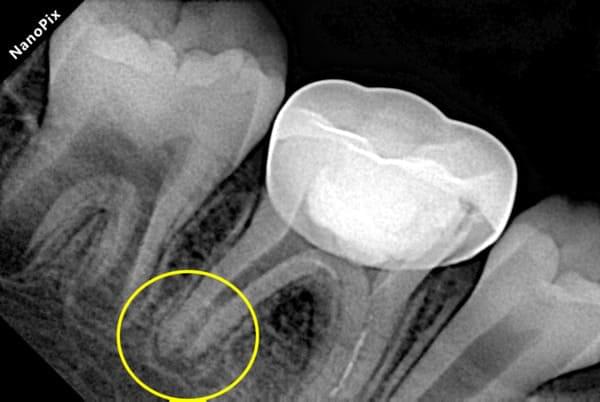

Проблема виникає, коли нерв (пульпа) постійного зуба передчасно гине від травми чи інфекції. Це критично, адже саме пульпа відповідає за ріст кореня. Без неї корінь залишається коротким і тонким. Такий зуб не може витримувати жувальне навантаження і ризикує бути втраченим. Це як дерево з великою кроною та маленьким корінцем: найменший вітер може його вирвати.

Завдяки науковим дослідженням ми знаємо, що навколо кореня зуба є стовбурові клітини. Наша методика дозволяє створити в зубі спеціальні умови, щоб ці стовбурові клітини мігрували в кореневий канал. Там вони перетворюються на клітини, схожі на клітини пульпи, і відновлюють ріст кореня — як у довжину, так і в товщину.